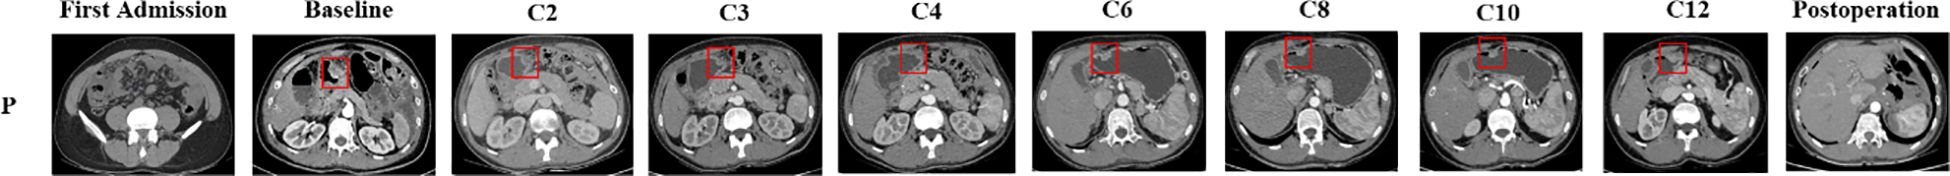

Gastric cancer, a leading global cause of cancer-related mortality, is frequently diagnosed at advanced stages with peritoneal metastasis, significantly limiting curative options. Current strategies integrate systemic chemotherapy, hyperthermic intraperitoneal chemotherapy (HIPEC), and targeted therapies, yet outcomes remain suboptimal. Claudin18.2, a tight junction protein overexpressed in 27.4–52% of gastric cancers, has emerged as a novel therapeutic target, with recent Phase III trials demonstrating survival benefits for Claudin18.2-targeted monoclonal antibodies in HER2-negative advanced disease. However, the synergy of HIPEC with Claudin18.2-targeted therapies remains unexplored. This study presents a case of Claudin18.2-positive advanced gastric adenocarcinoma with peritoneal metastasis treated with a multimodal regimen: HIPEC, systemic CapeOx chemotherapy, and Claudin18.2-targeted therapy (ASKB589). Following 12 cycles, imaging and tumor markers (CA125, CEA) normalized, enabling curative gastrectomy. At 893 days post-diagnosis, the patient remains disease-free (PFS/DFS: 893/573 days) on adjuvant capecitabine. Treatment-related toxicities (predominantly Grade 1-3 hematologic and gastrointestinal events) were manageable. This case highlights Claudin18.2 as an actionable biomarker and proposes a "local-systemic" synergy model for peritoneal-metastatic gastric cancer. However, the absence of cytoreductive surgery and single-case limitations necessitate validation through randomized trials. Future research should prioritize biomarker-driven HIPEC protocols (e.g., nanoparticle-enhanced Claudin18.2-targeted delivery) and dynamic monitoring of Claudin18.2 expression during therapy.